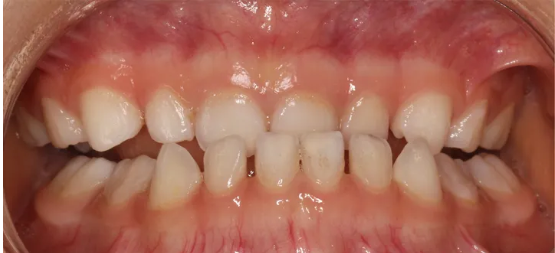

就像这位小朋友是嘴凸的问题,上颌前凸,下颌后缩,通过早期矫正后10个月时间面型和牙齿咬合带来的巨大变化。

孩子家长也比较注重孩子的牙齿咬合健康,所以利用孩子寒暑假的时间给孩子做早期矫正,通过早期矫正,使孩子的牙齿咬合和面型都得到很好的改善。